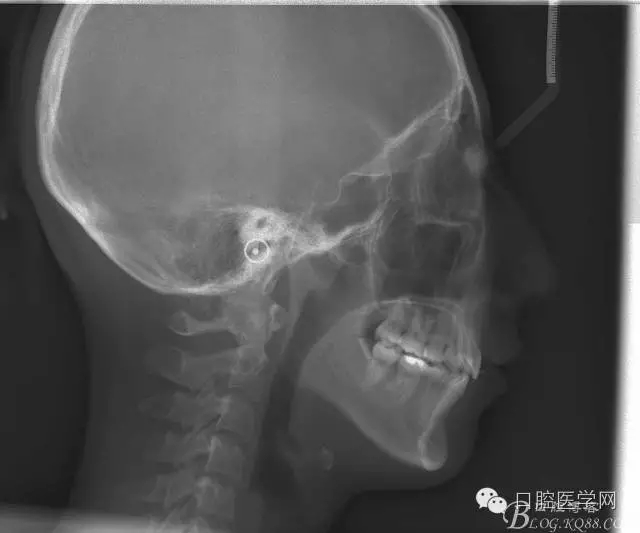

正畸查:替牙合。第一恒磨牙中性合。上牙弓尖圓型下牙弓方圓型。前牙覆合3度覆蓋7.5mm。下前牙咬到上舌側(cè)牙齦。上頜擁擠4.0mm,下頜擁擠

3.0mm。上頜稍前突下頜后縮,上下唇前突,上前牙覆蓋下唇,下唇外翻。面下三分之一過(guò)短,頦唇溝明顯,開(kāi)唇露齒,頦饜窩明顯。顳下頜關(guān)節(jié)開(kāi)閉口無(wú)彈響,無(wú)壓痛,開(kāi)口型開(kāi)口度正常。

設(shè)計(jì):

1:SWA.

2:拔牙矯治,拔出4顆第一前磨牙。

3:上下頜利用拔牙間隙解除擁擠并內(nèi)收上下前牙,改善唇側(cè)貌。

4:導(dǎo)下頜向前改善頜面?zhèn)让病?/p>

5:上頜TPA+NanceArch強(qiáng)支抗.

6:下頜囊腫開(kāi)窗引流,雙側(cè)第一恒磨牙舌桿保持牙位。擇期拔除第一前磨牙。